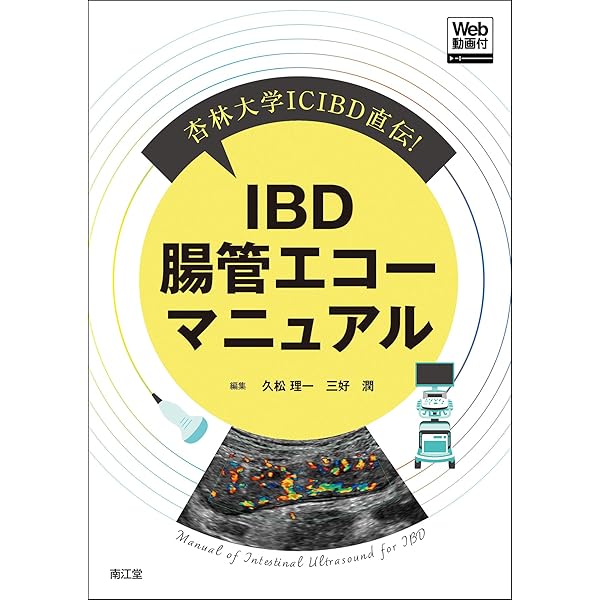

消化管エコーの診かた・考え方第2版

医学書院

2004/04/01

4260106546

9784260106542

消化管エコーの診かた・考え方第2版

医学書院

2004/04/01

4260106546

9784260106542